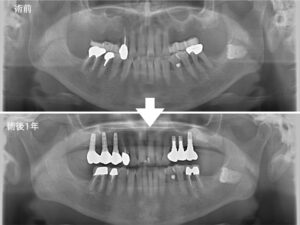

‎20260429_インプラント.‎002 | さとう歯科クリニック 南区妹尾